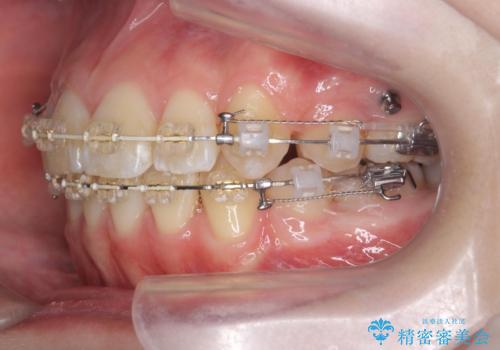

突き出た前歯を治したい 小臼歯抜歯+マルチブラケット矯正

- 矯正装置

- ワイヤー矯正

- 治療期間

- 2年8ヶ月

- 突き出て、気になる前歯の角度の改善を求めて来院されました。

前歯の角度を改善するために小臼歯4本の抜歯を行いワイヤー マルチブラケットを用いて、しっかりと前歯の角度を改善する治療計画としました。

綺麗な歯並びを手に入れられたと同時に、口元もスッキリし、仕上がりに満足いただくことができました。